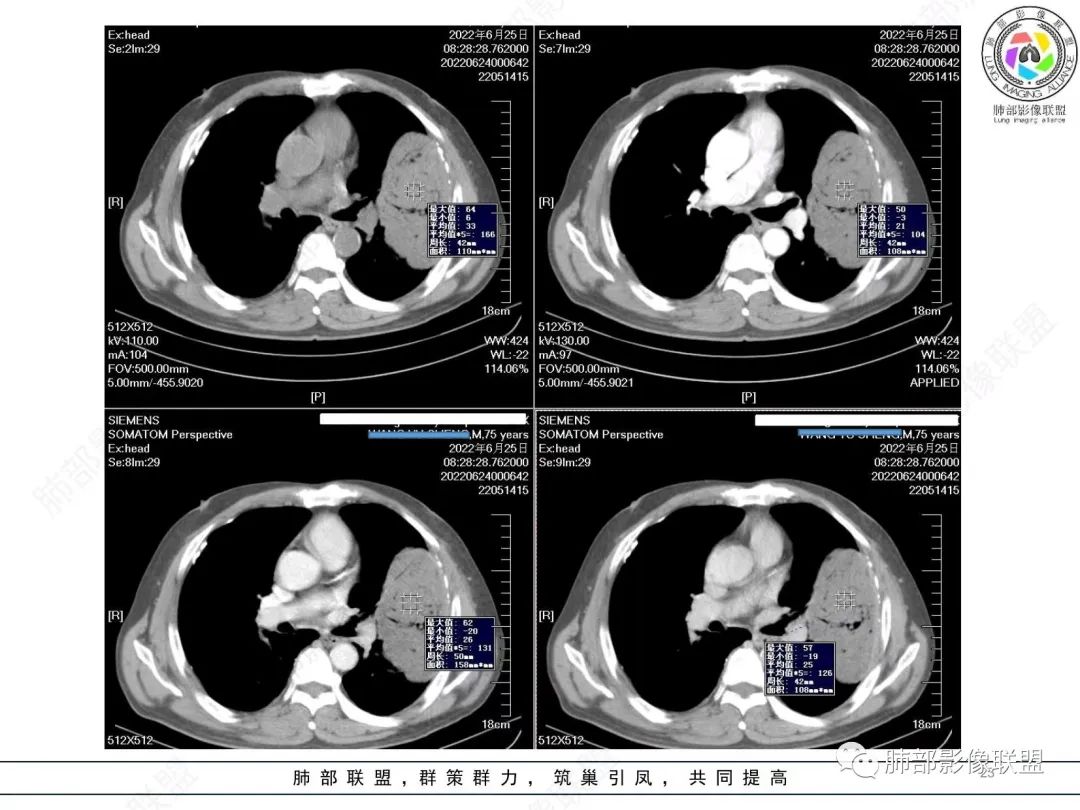

我再建一下血管。支气管进入,但是近端推移,堵塞

大肿块,边缘光滑,深分叶

近端支气管堵塞、推移为主

部分类似于脐凹征

内部支气管扩张

肺动脉推移为主,边缘部分进入

大肿块、表面光滑但深分叶,肺门侧支气管堵塞

回头看,内部支气管近端其实不连续,伴随肺动脉不存在

4)密度:肿块平扫为软组织密度,由于体积较大,内部常见大片状坏死,可出现不规则厚壁空洞或坏死内多发无壁小空洞,坏死多不均匀:坏死灶内可见如柳絮样的斑片样强化灶,坏死边缘与非坏死区分界不清本例坏死较明显,密度不均匀。

5)肿瘤强化方式:肺部恶性肿瘤强化程度与其血供丰富程度相关,血供丰富多强化明显,反之则较差。由于PSC 周边实性部分富血供及内部黏液变性、坏死,增强后肿块多数呈轻-中度边缘环形强化或不均匀小斑片状强化。国外学者对照病理发现肿瘤细胞或胶原组织增强扫描时强化,无强化的低密度区代表了黏液样变性区和出血坏死区。